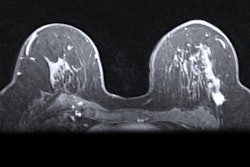

Contrast-enhanced mammography exam of both breasts in two views. In the first two low-energy images (A, B), an ill-defined mass can be seen in the upper outer quadrant of the right breast at the location of a palpable mass in a 52-year-old patient. In the left breast, no relevant abnormalities can be detected. In the recombined images (C, D) of a contrast-enhanced mammography examination, contrast uptake can be appreciated. The recombined images show an irregular enhancing mass in both breasts -- both in the upper outer quadrant. Tissue sampling revealed a bilateral invasive breast cancer of no special type. A breast MRI examination performed prior to surgery also confirmed the presence of two irregular enhancing masses on these contrast-enhanced T1 weighted images (E: top example is the cancer in the right breast; bottom example is the left breast). All images courtesy of Dr. Marc Lobbes, PhD.